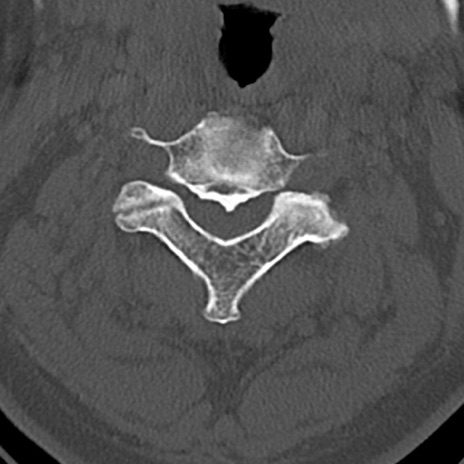

頚椎CT

横断像